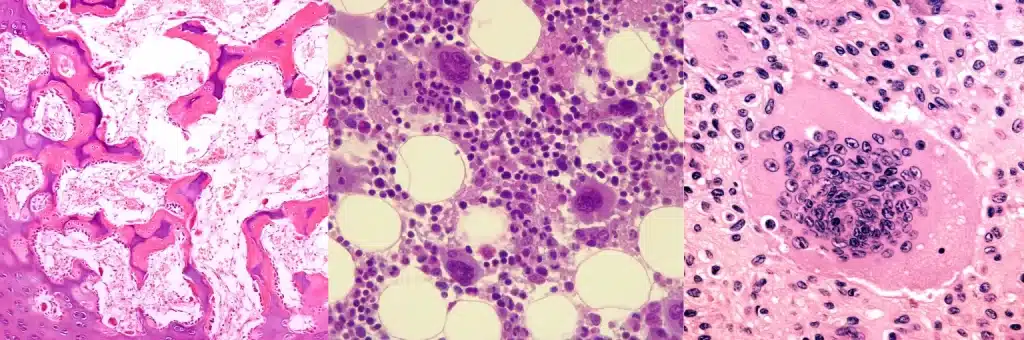

รู้จักเซลล์กระดูก 3 ชนิดหลัก

เซลล์กระดูกแต่ละชนิดมีหน้าที่เฉพาะที่ประสานกันอย่างลงตัว การทำงานร่วมกันของเซลล์กระดูกทั้ง 3 ชนิดนี้เป็นกลไกสำคัญที่ส่งผลต่อการเจริญเติบโตด้านความสูง

เซลล์สร้างกระดูก (Osteoblast)

เซลล์สร้างกระดูก หรือ Osteoblast มีหน้าที่คอยสร้างเสริม พัฒนาโครงสร้างกระดูกให้แข็งแรง เซลล์ชนิดนี้มีความสำคัญอย่างยิ่งต่อการเจริญเติบโต และการพัฒนาความสูงในเด็ก โดยทำหน้าที่หลักในการสร้างเนื้อกระดูกใหม่ผ่านกระบวนการผลิตคอลลาเจน พร้อมกับโปรตีนพิเศษที่จำเป็นต่อการเจริญเติบโต

เซลล์กระดูก (Osteocyte)

เซลล์กระดูก หรือ Osteocyte เป็นเซลล์ที่มีความซับซ้อน ทำหน้าที่สำคัญในการควบคุมระบบกระดูกทั้งหมด คอยดูแลทุกส่วนให้ทำงานประสานกันอย่างมีประสิทธิภาพ เซลล์ชนิดนี้มีลักษณะพิเศษคือมีแขนงยื่นยาวเชื่อมต่อกับเซลล์อื่นๆ ทำให้สามารถส่งสัญญาณ และตอบสนองต่อการเปลี่ยนแปลงต่างๆ ได้อย่างรวดเร็ว

เซลล์ทำลายกระดูก (Osteoclast)

เซลล์ทำลายกระดูก หรือ Osteoclast เป็นเซลล์ที่แม้จะมีชื่อว่า “เซลล์ทำลาย” แต่แท้จริงแล้วมีความสำคัญอย่างยิ่งต่อการเจริญเติบโต และการปรับตัวของกระดูก ทำงานอย่างมีประสิทธิภาพแม่นยำ